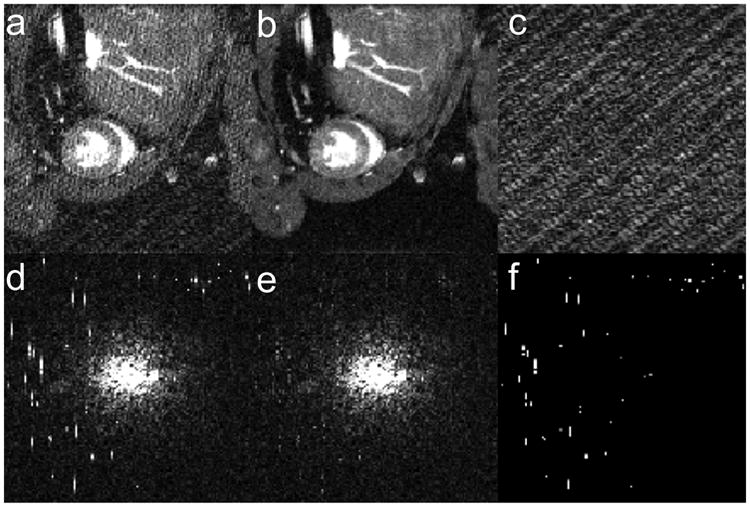

Figure 3.

Images (a-c) and k-space data (d-f) for a single frame of the cine data set. Corrupted data (a, d) is decomposed into low-rank (b, e) and sparse (c, f) components to isolate RF spikes (visible in f) and remove stripe artifact (visible in a). All cine frames are shown in Video 3 (online supporting information).

Furthermore, the mouse heart cine data was used to demonstrate the application of this algorithm to a single frame or static image (Figure 4). The broad central k-space peak in the cine images makes this a challenging test of the single frame application of the RPCA despiking algorithm. The optimal κ was 3 for the static image. In this case, the RPCA algorithm performs well and isolates RF-spikes similarly to the multi-frame cine data set. However, much of the peaked central cluster is initially incorrectly placed in the sparse matrix, which is then corrected in the center refilling step of the algorithm. Specifically, for the cardiac cine data set with 20 frames, an average of 70 pixels of the central region (of the possible 256 pixels) were misclassified as sparse. In comparison, applying the algorithm to a static frame from this data set, 161 pixels of the central region were misclassified.